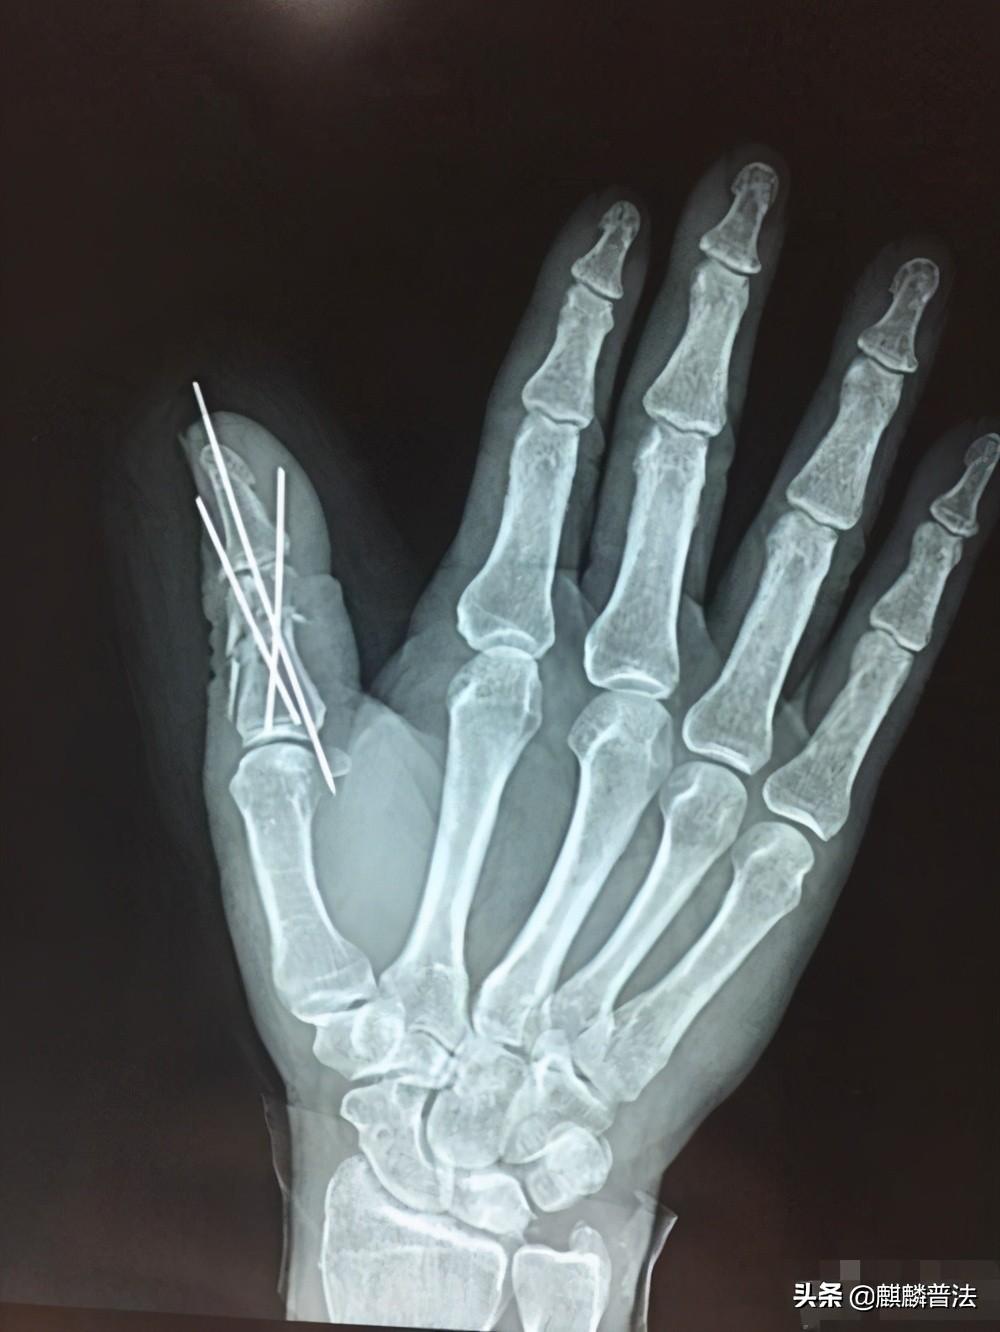

陈某于2015年7月1日入职广东某公司,担任泵车操作员一职,月工资为5500元,对公账户发放。双方未签订劳动合同,公司亦未为陈某缴纳社会保险,2016年5月2日中午12时,陈某在工地工作时不慎被其同事操作的泵车压伤,经医院诊断为右拇指开放性粉碎性骨折。